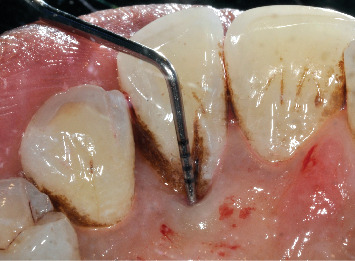

本病例报告讨论了成功处理与III期广泛性C级牙周炎相关的腭深发育沟。尽管先前进行了非手术牙周治疗,但病情进展迅速,需要进一步干预。综合评估显示广泛性牙周炎与局部牙齿相关的易感性因素,由于发育沟在重要的左上侧切牙。最初的非手术治疗包括刮除和根刨(SRP)以及全身抗生素。除发育凹槽部位外,其他部位均有显著改善。手术干预使用腭通道瓣牙成形术和根根成形术来消除剩余的袋和加强菌斑控制。手术成功地解决了问题,在6个月的随访中观察到软组织愈合,残余探探深度为3mm。本病例强调了与腭发育沟相关的挑战,作为牙周炎的局部加重因素。手术技术的使用,如牙成形术和皮瓣访问被证明是有效的管理牙周缺损相关的发育沟,展示了一个成功的结果在这个病人。

This case report discusses the successful management of a deep palatal developmental groove associated with Stage III generalized Grade C periodontitis. Despite prior nonsurgical periodontal therapy, the disease progressed rapidly, necessitating further intervention. A comprehensive evaluation revealed generalized periodontitis with localized tooth-related predisposing factor due to a developmental groove in the vital upper left lateral incisor. The initial nonsurgical treatment involved scaling and root planing (SRP) coupled with systemic antibiotics. Significant improvement was observed, except for the site with the developmental groove. Surgical intervention was performed using a palatal access flap odontoplasty and radiculoplasty to eliminate the remaining pocket and enhance plaque control. The procedure successfully resolved the condition, with soft tissue healing observed at the 6-month follow-up with a residual probing depth of 3 mm. This case highlights the challenges associated with palatal developmental grooves as localized aggravating factors in periodontitis. The use of surgical techniques like odontoplasty and flap access proved effective in managing periodontal defects associated with developmental grooves, showcasing a successful outcome in this patient.